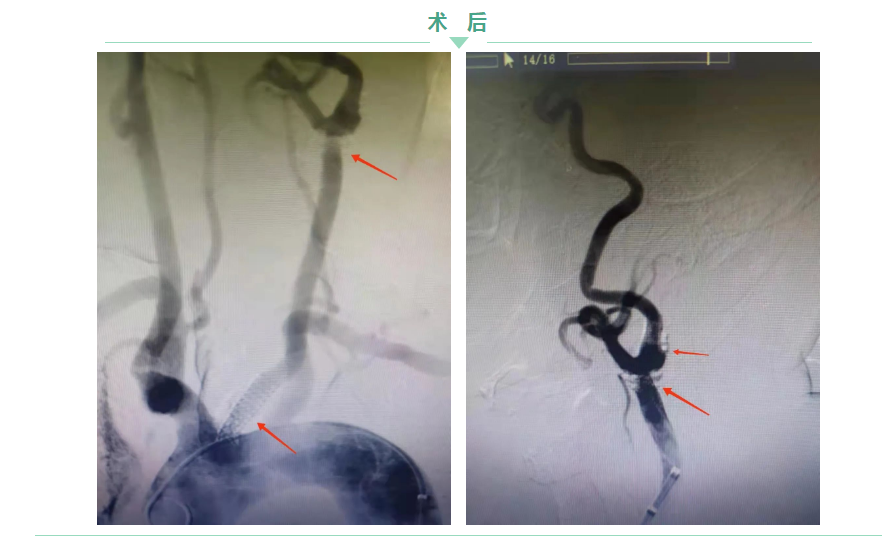

神經(jīng)內(nèi)科主任鐘濤與血管介入科主任劉綿春,聯(lián)合為王大爺實施支架植入術(shù),雖然在手術(shù)過程中遇到了各種難題,但鐘主任與劉主任“見招拆招”,手術(shù)順利結(jié)束。 兩處支架完全覆蓋患者的狹窄斑塊,血流通暢了。

術(shù)后第二天,王大爺?shù)念^暈、頭痛癥狀明顯緩解,感覺頭腦“清亮”了。目前,王大爺已康復(fù)出院。